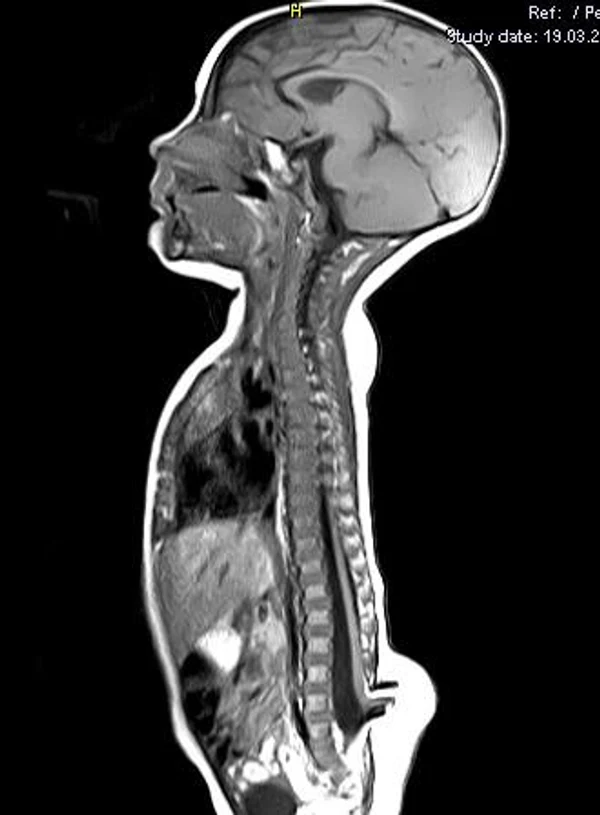

Spina bifida, спинно-мозговые грыжи, диастематомиелия, липоменингомиелолоцеле, фиксированный спинной мозгSpina bifida включают различные типы нарушения закладки и развития нервной трубки на спинальном уровне, что сопровождается незаращением дужек позвоночника и часто сопровождается одновременным пороком развития спинного мозга и его оболочек. Встречаются у 1 на 1000 – 3000 новорожденных. Могут наблюдаться в различных отделах позвоночника, но наиболее часто встречается в пояснично-крестцовом отделе. Незаращение дужек позвонков с наличием грыжевого выпячивания обозначается в литературе по разному: спинно-мозговые грыжи, spina bifida, spina bifida cystica, spina bifida vera, spina bifida typica, spina bifida aperta. Классификация spina bifida aperta: I Рахишизис. II Спинномозговые грыжи. Менингоцеле. Менингорадикулоцеле. Миеломенингоцеле. Миелоцистоцеле. Липоменингомиелоцеле. Основные сопутствующие пороки центральной нервной системы: Гидроцефалия до 65-85%. Аномалия Киари 2. Сирингомиелия.